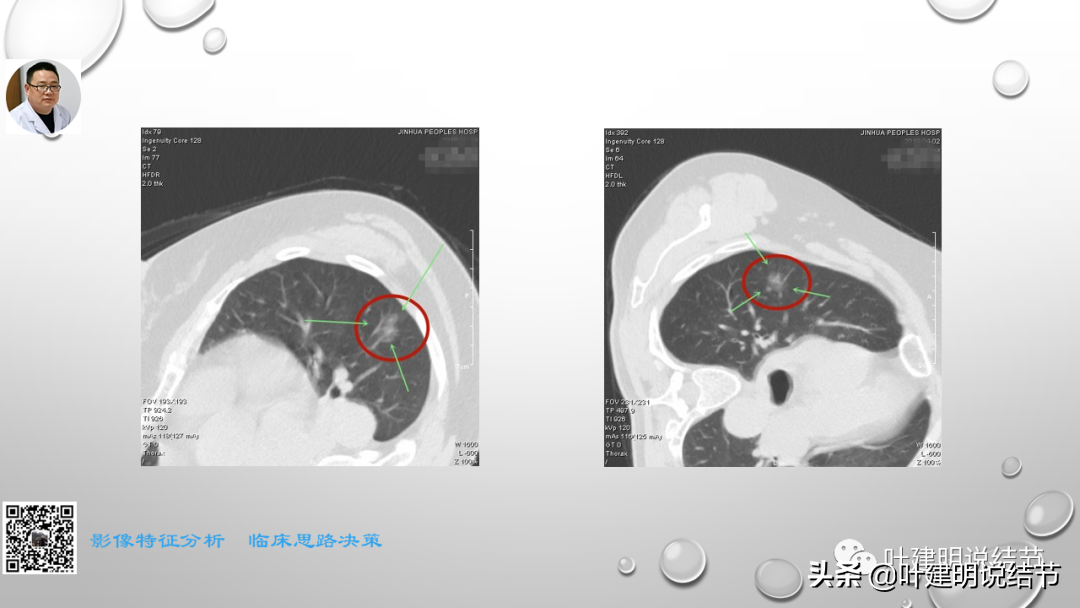

这次讲课的第三部分是阐述对于磨玻璃为表现的早期肺癌自己的观点与理念以及相应思考的精髓部分。也是我一直坚持不懈宣传、普及的思想。也许目前只是想法而已,因科研水平能力所限,无法转换为循证依据来证实其正确性。但我想我们的呼吁总也会引起有相关科研能力同道的注意,从而在未来得以验证并改写指南或出台专门针对肺磨玻璃结节为表现的早期肺癌的诊疗规范或指南。如果真有这种事情发生,那么自己的所作所为将是意义非凡的!